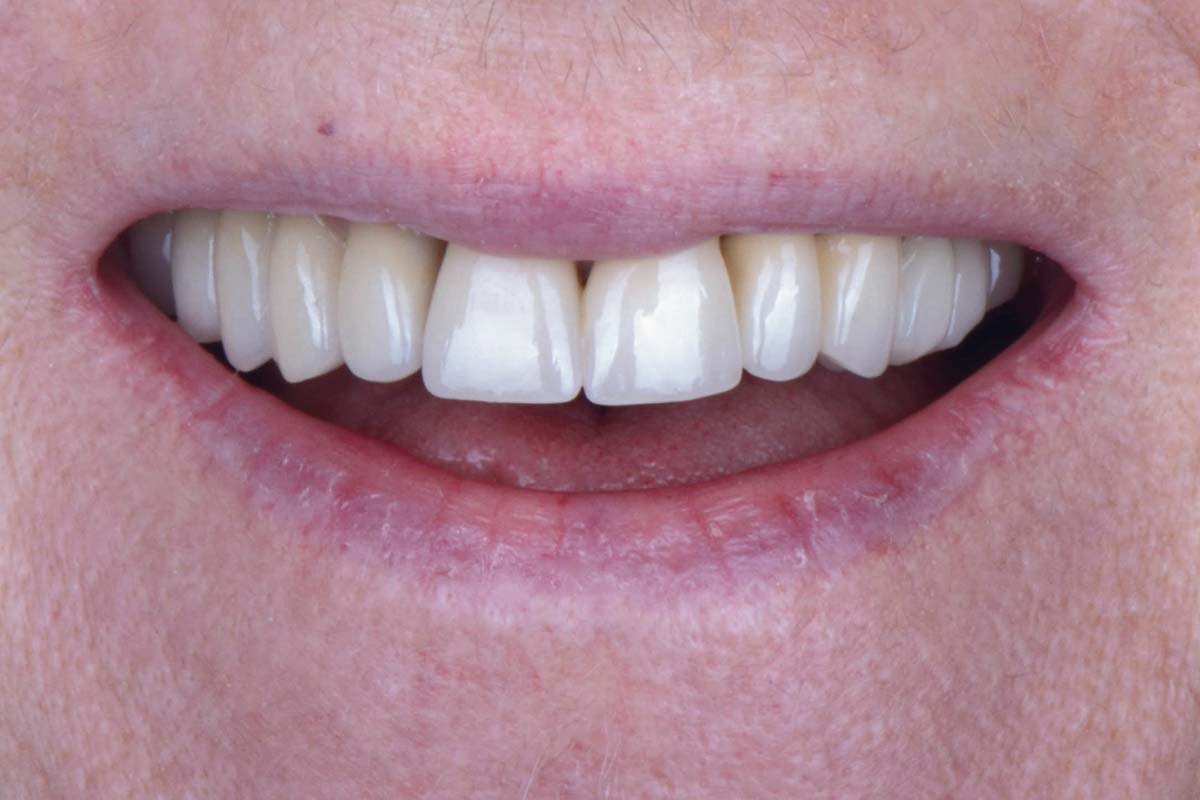

Smile rehabilitation in the anterior maxilla with maxgraft® bonebuilder - Dres. A. Dagba and J. Mourlaas